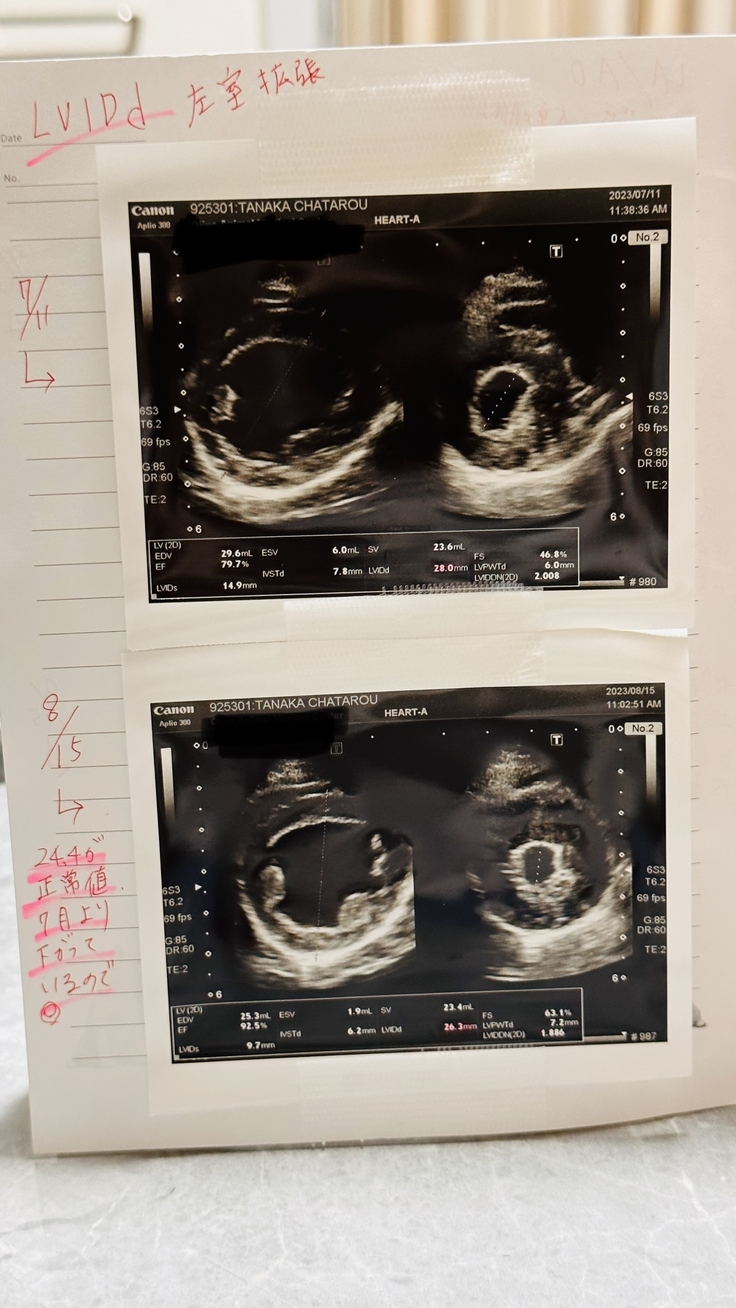

LVIDd(左室拡張)*正常値が24.4mm

正常値よりは高めですが、7月の検査時より下がってきているので◎

前回7月→28.0mm

今回8月→26.3mm